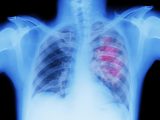

8月8日、英紙「The Daily Mail」をはじめとする複数の海外メディアが報じたところによると、米名門大の南カリフォルニア大学が行った最新研究で「フライパンなどの台所用品に含まれる“永遠の化学物質”が、肝臓がん(非ウイルス性)のリスクを4~4.5倍に高める可能性がある」と新たに判明したという。

研究チームはロサンゼルスとハワイに住む20,000人以上の医療データを分析、肝臓ガンを発症した50人と発症していない50人の血液サンプルを比較したところ、ガンを発症した被験者の血液には複数の「永遠の化学物質」が含まれ、その量が多いほどリスクが高まる傾向が見られた。

「永遠の化学物質」は肝臓の代謝に悪影響を与え、非アルコール性脂肪肝(NAFL、アルコール摂取に関連しない肝臓疾患)を発症し、やがて肝臓がんに至る危険性が高まるが、すでに25%のアメリカ人がNAFLを抱え、2030年にこの割合は30%にまで増える恐れがあるようだ。